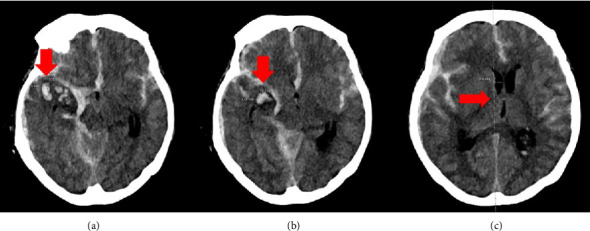

Remimazolam is a short-acting benzodiazepine that was approved by the United States Food and Drug Administration (FDA) in 2020 for the induction and maintenance of procedural sedation in adults undergoing procedures lasting 30 min or less. Given its recent introduction, the use of remimazolam for general anesthesia and monitored anesthesia care (MAC) remains an area of ongoing investigation. In this report, we present the first documented case demonstrating that remimazolam can achieve hemodynamic stable burst suppression in a critically ill patient undergoing emergent craniectomy and aneurysm clipping. Additionally, this manuscript reviews the reported off-label applications of remimazolam in both the operating room and the intensive care unit (ICU) settings.